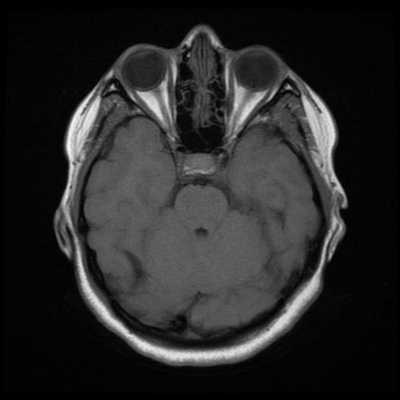

Гемимегалэнцефалия (ГМЭ) или унилатеральная мегалэнцефалия — дисплазия головного мозга, обусловленная унилатеральными нарушениями нейронной миграции и пролиферации, результатами которых является одностороннее диспластическое увеличение одной из гемисфер (В.А. Чадаев и соавт., 2003). Гемимегалэнцефалия может встречаться как изолированный порок, так и сочетаться с гемигипертрофией всего тела — синдром Клиппель-Треноне-Вебера (Anlar B. и соавт., 1988); нейрокожными синдромами: протеуса, линейного невуса, эпидермального невуса, гипомеланоза Ито, нейрофиброматоза, туберозного склероза (De Lone D.R. и соавт., 1999; Sasaki M. и соавт., 2000).

Облигатным признаком ГМЭ является чрезмерное развитие одной гемисферы при нормальных размерах другой. Нарушение устройства рисунка извилин (сулькации) может быть представлено участками коры с увеличенными, утолщенными (пахигирия) или удлиненными и истонченными (полимикрогирия) зонами. В гипертрофию обычно вовлекаются глубинные структуры полушарий, реже мозжечок. Гемигипертрофия ствола мозга или спинного мозга является редкостью (Tuxhorn I. и соавт., 1997). Диспластические нарушения могут обнаруживаться и в контралатеральном «здоровом» полушарии.

Диагноз ГМЭ в современных условиях устанавливается, в подавляющем большинстве случаев, при МРТ исследовании головного мозга. МРТ у больных с ГМЭ выявляет асимметрию гемисфер за счет диффузно увеличенного, аномального полушария. Характерна вентрикуломегалия диспластичной гемисферы. В Т2 — режиме выявляется интенсивный сигнал в белом веществе — результат сочетания глиоза и участков гипомиелинизации.

Гемимегалэнцефалия - увеличение размера части или всего полушария большого мозга.

Определяют асимметрию полушарий или долей мозга. В увеличенном полушарии в большинстве случаев находят гетеротопию, которая может деформировать боковой желудочек. Боковой желудочек расширен, а его передний рог компримирован и выпрямлен. Борозды и извилины деформированы, могут обнаружиться участки пахигирии, полимикрогирии. Граница между серым и белым веществом смазанная, нечеткая. На Т2-ВИ интенсивность сигнала от белого вещества бывает повышена вследствие демиелинизации. В субкортикальных отделах пораженного полушария могут определяться кистозные изменения.